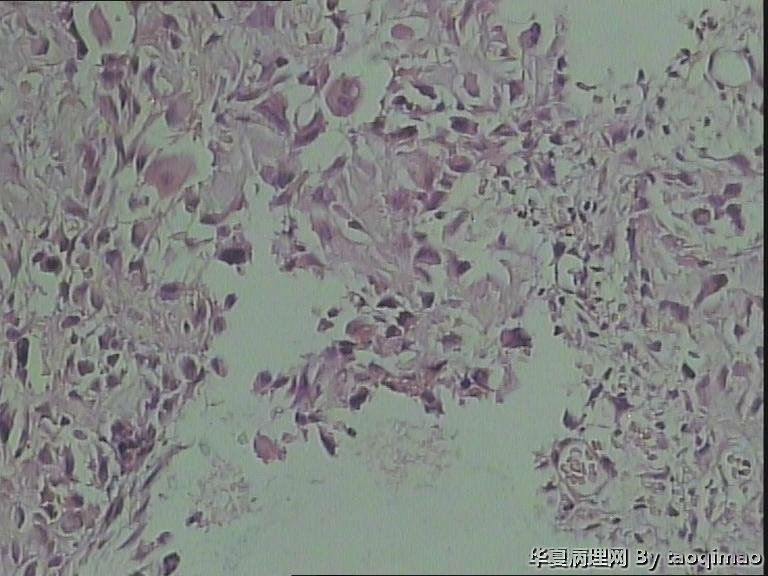

• 肋骨肿物,求助图2

图2

患者女,31岁,胸部CT第八肋骨肿瘤,肿物在肋骨内突出骨外膜,大小2.3X1.5.切面灰白质韧

这是一部分容易取下来的肿瘤,其余部分还在脱钙中

骨母细胞瘤。矿化不均要除外骨母细胞型骨肉瘤,虽然肿块小了点。还是找找核分裂,看看X线的好。

那就是骨样骨瘤。